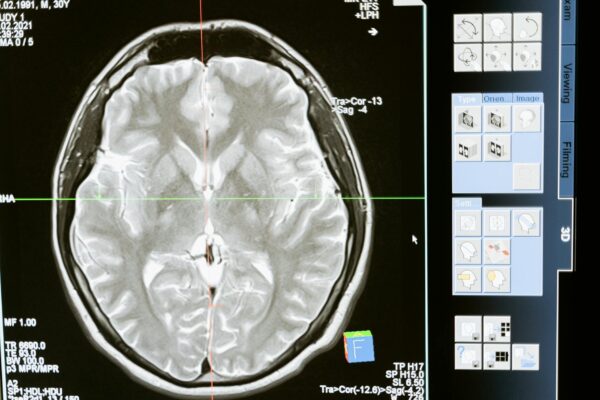

Már az emberi agyban is kimutathatók a mikroszkopikus méretű műanyagdarabkák

Manapság már szinte lehetetlen olyan helyet találni a bolygón, ahol ne bukkannának fel a műanyagmaradványok. Legyen szó a legmélyebb óceáni árkokról vagy a legmagasabb hegycsúcsokról,...